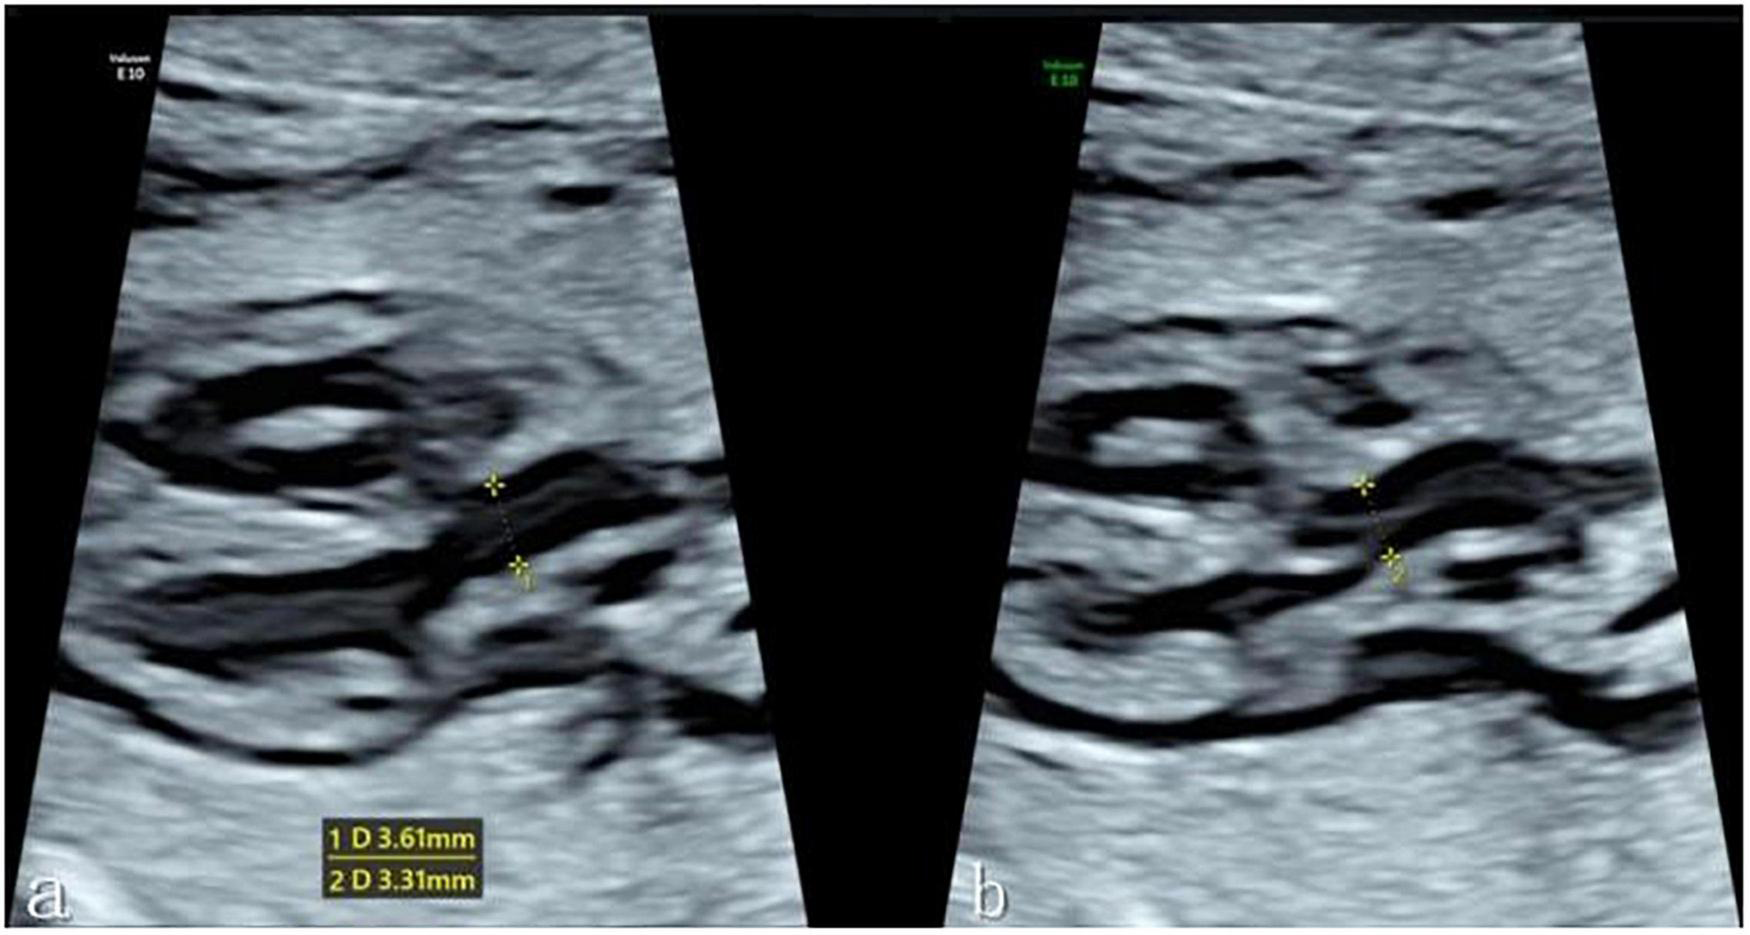

The fetal left ventricular outflow tract view was then clearly displayed in the instrument fetal heart mode, with the ultrasound beam and ascending aorta long axis kept as vertical as possible to ensure a clear display of the echo of the tube wall. When the fetus had no obvious movement, one investigator (C.FL.) obtained a clear image of the left ventricular outflow tract section, and the Dmax and Dmin of the ascending aorta were evaluated at the sinotubular junction at the end of systole and end of diastole, respectively. End-systole is defined as the frame before the aortic valve closes, while end-diastole is defined as the frame before the aortic valve opens. When measuring the inner diameter of the sinotubular junction, the target was expanded to fill more than 1/3 of the screen, a caliper was placed on the tube wall, and the distance between inner edges was measured (see Figure 1). Each data point was measured three times before an average was determined. The ascending aorta diameter expansion rate was then computed as follows: Diameter Distensibility (100%) = (Dmax-Dmin)/Dmin*100%.

FIGURE 1

(a) Measurement of the Dmax of the ascending aortic sinotubular junction at the end of systole in the left ventricular outflow tract view. (b) Measurement of the Dmin of the ascending aortic sinotubular junction at the end of diastole. *Caliper.